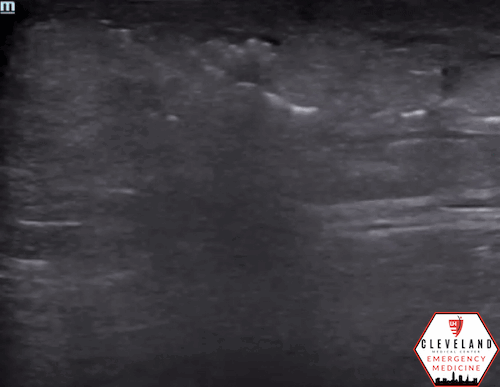

• Establish normal: Begin scanning away from the affected area to appreciate normal soft tissue appearance, see Figure 1.

Figure 1. Normal skin, subcutaneous tissue, and fascia [8].